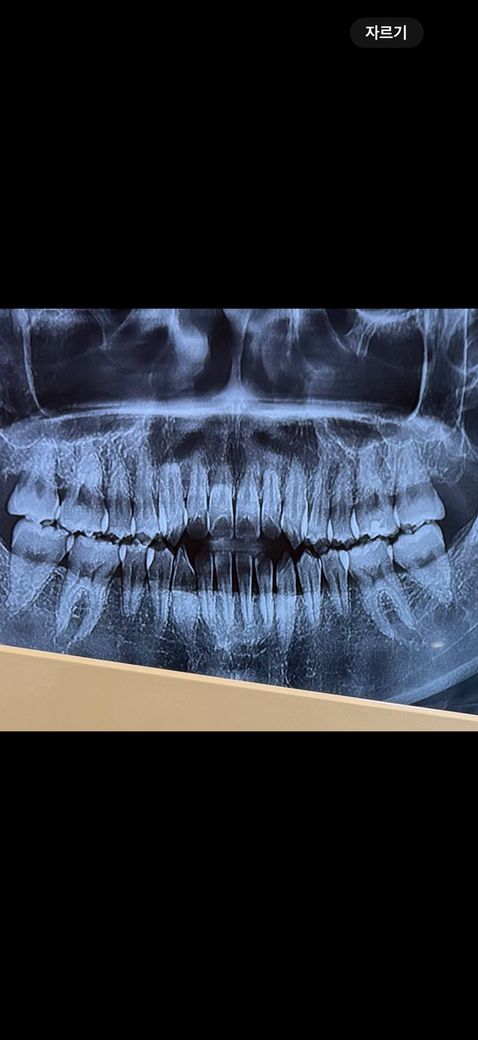

우연히 양치를 하나 봤는데 위 앞니양쪽 에 가로 금이 있더라구요 ㅠㅠ 특히 오른쪽이 좀더 진하구요(사진상은 반대에요) 그냥 외관상 봤을때는 첫번째 사진 파란 네모안에 처럼 좀 금이 살짝 보이는정도고 각도에 따라서 두번째 사진에 보라색 네모친 부분처럼 그림자처럼 보이기도해요 근데 확실히 플래쉬를 비추면 세번째 사진 초록색 네모부분안에 금이 훨씬 잘보여요 ㅠㅠ 혹시나해서 안쪽도 보니 금이 살짝있는데 바깥 금이랑은 같은 위치인지는 모르겠는데 네번째 사진상으로 안나와서 대충 그려서 올립니다! 검은 색 선처럼 약간 가로금이있어요 그런데 제가 원래부터 앞니에 세로로 된 실금은 좀 있었는데 가로로 된 실금은 처음봤어요 ㅠㅠ 그동안 앞니에 큰 충격은 따로 없었고 있어봤자 양치하다 칫솔에 앞니 부딪히는정도가 끝이었어요 몇주전 한번 금있는 치아가 갑자기 시리거나 물 닿았을때 시린건 한번씩 있었는데 그 뒤로는 불편한 건 없었고 금이 만져지거나 하지도않아요 그리고 무엇보다 이번년도 4월에 정기검진했는데 엑스레이도 촬영했는데 이때도 치아 금은 보이지않는다 그러셨거든요 ㅠㅠ 혹시몰라 마지막사진 첨부합니다 이때 금이 있었는지는 모르겠으나 이상없다하셨는데 외상이 없는데 갑자기 금이 생길수 있나요…? 제가 근데 개방교합이라 윗니들이 간격이 좁아서 살짝 튀어나오고 뒤틀어진건 있습니다 ㅠㅠ 일단 사진 보시기에 치료가 필요한 수준인가요..?😭 임플란트 해야할까봐 무서워요 ㅠㅠ 꼭 답변 부탁드릴게요..

• 4번 째 사진